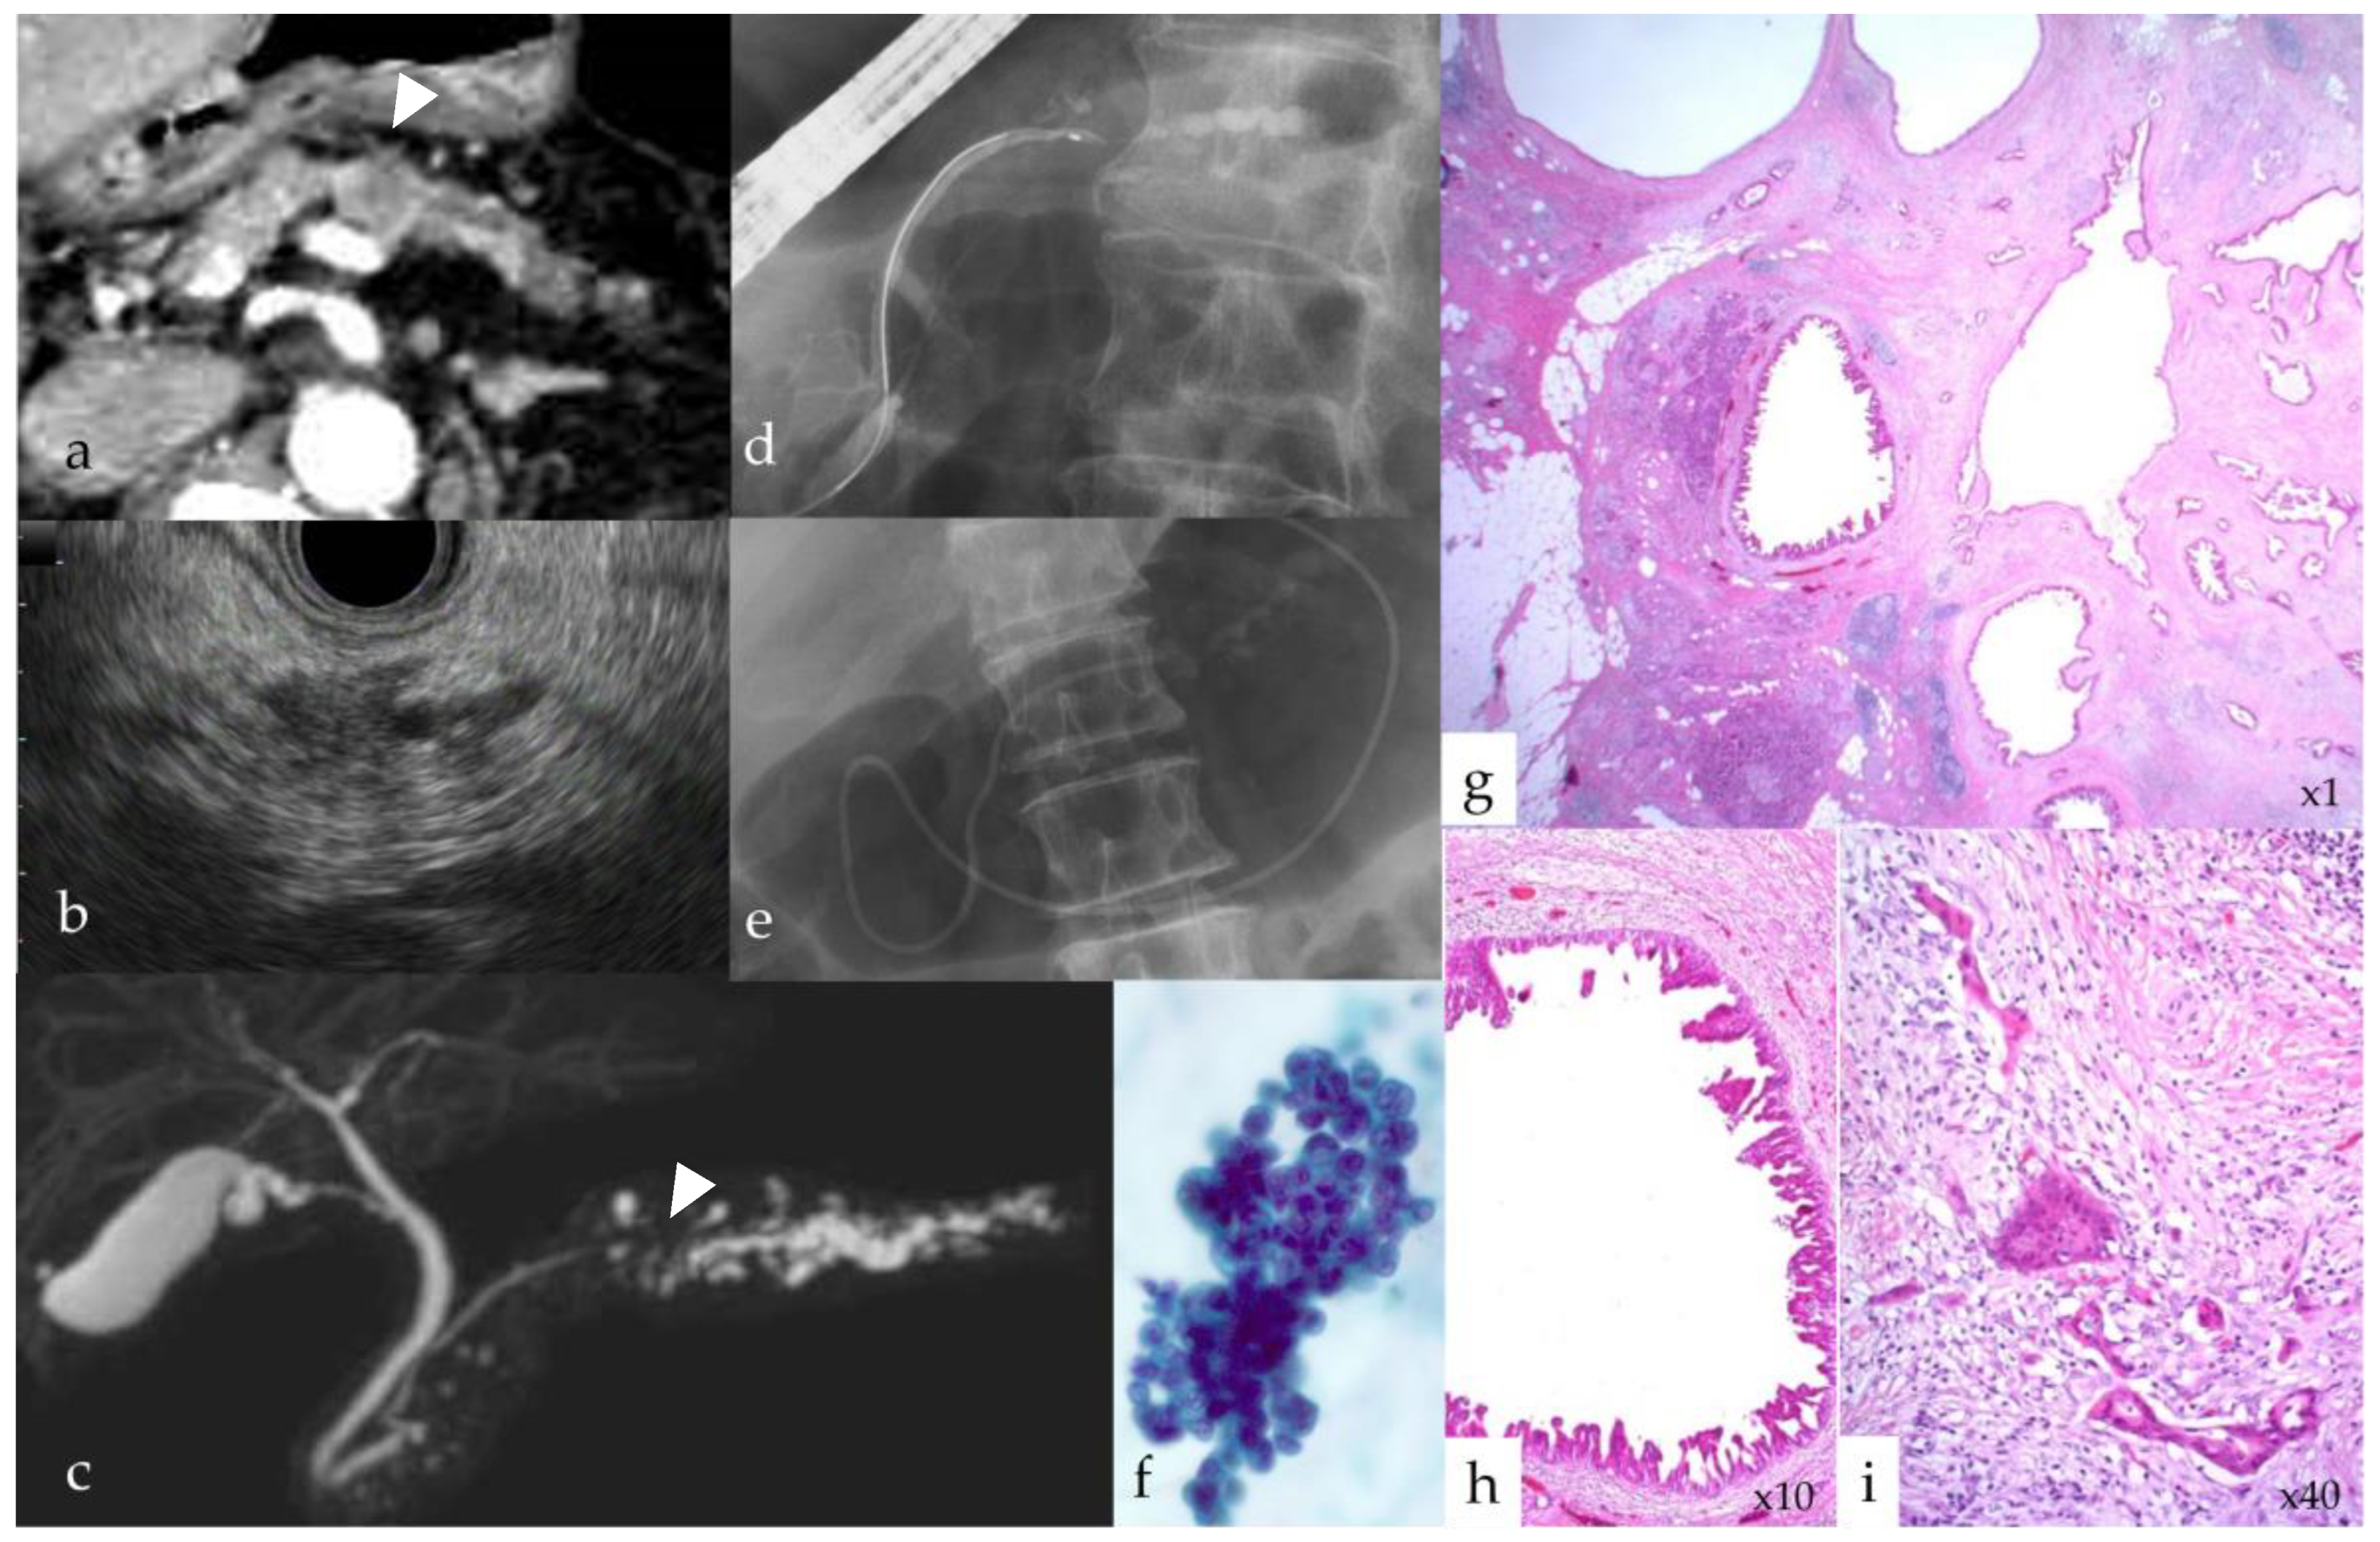

2.2.2. Imaging Diagnosis of Stage 0 and IA PC

2.2.3. Pathological Diagnosis of Stage 0 and IA PC

- Hanada, K.; Fukuhara, M.; Minami, T.; Yano, S.; Ikemoto, J.; Shimizu, A.; Kurihara, K.; Okuda, Y.; Ikeda, M.; Yokode, M.; et al. Pathological features and imaging findings in pancreatic carcinoma in situ. Pancreas 2021, 50, 399–404. [Google Scholar] [CrossRef] [PubMed]

- Hanada, K.; Okazaki, A.; Hirano, N.; Izumi, Y.; Teraoka, Y.; Ikemoto, J.; Kanemitsu, K.; Hino, F.; Fukuda, T.; Yonehara, S. Diagnostic strategies for early pancreatic cancer. J. Gastroenterol. 2015, 50, 147–154. [Google Scholar] [CrossRef]

- Sagami, R.; Yamao, K.; Nakahodo, J.; Minami, R.; Tsurusaki, M.; Murakami, K.; Amano, Y. Pre-oerative imaging and pathological diagnosis of localized high-grade pancreatic intra-epithelial neoplasia without invasive carcinoma. Cancers 2021, 24, 945. [Google Scholar] [CrossRef]

- Yamao, K.; Takenaka, M.; Ishikawa, R.; Okamoto, A.; Yamazaki, T.; Nakai, A.; Omoto, S.; Kamata, K.; Minaga, K.; Matsumoto, I.; et al. Partial pancreatic parenchymal atrophy is a new specific finding to diagnose small pancreatic cancer (≤10 mm) including carcinoma in situ: Comparison with localized benign main pancreatic duct stenosis patients. Diagnostics 2020, 10, 445. [Google Scholar] [CrossRef]

- Nakahodo, J.; Kikuyama, M.; Nojiri, S.; Chiba, K.; Yoshimoto, K.; Kamisawa, T.; Horiguchi, S.; Honda, G. Focal parenchymal atrophy of pancreas: An important sign of underlying high-grade pancreatic intraepithelial neoplasia without invasive carcinoma, i.e., carcinoma in situ. Pancreatology 2020, 20, 1689–1697. [Google Scholar] [CrossRef]

- Kurihara, K.; Hanada, K.; Shimizu, A. Endoscopic ultrasonography diagnosis of early pancreatic cancer. Diagnostics 2020, 10, 1086. [Google Scholar] [CrossRef]